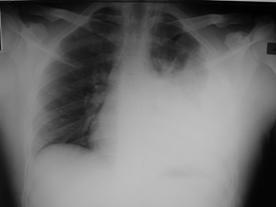

TRAUMATISME TORACICE

Pneumotorace sufocant bilateral Pneumotorace sufocant stang

Pneumotorace

sufocant stang Pneumotorace

sufocant drept Pneumotorace

sufocant drept